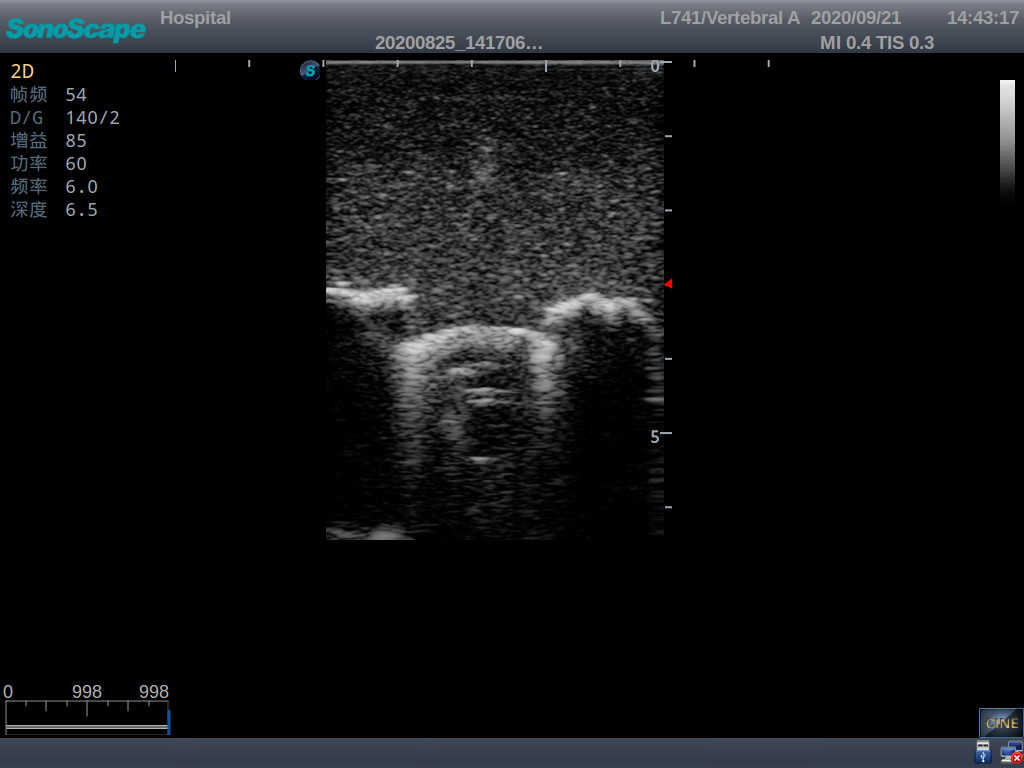

Pediatric Lumbar Puncture Ultrasound Training Model

This model is an ideal choice for ultrasound-guided pediatric lumbar puncture training with true-to-life skin feel and touch, accurate anatomical structures as well as real clinical ultrasound images. Realistic resistance to needle tips and correct landmarks provide excellent hands-on experience.

2)  Real clinical ultrasound images

1)  Ultrasound-guided lumbar puncture practice